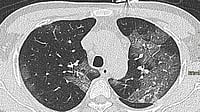

The body does try to fight back the viral invasion and Covid-19 seems to be a mild disease in most infected people. However, the loss of ACE2 shifts the balance towards higher and uncontrolled Angiotensin II and can make things go haywire. Indeed, higher levels of Angiotensin II increases vascular permeability in the lungs of many Covid-19 patients. The unbridled inflammation and oxidative stress (i.e. damage due to uncontrolled production of ROS) induced by hyperactive Angiotensin II can also fuel a vicious loop of damage to alveolar cells and pulmonary capillaries, hyperplasia (i.e. pathological increase of cell size) of the alveolar cells, formation of aberrant hyaline membranes and thick fibrosis in the damaged zones. WBCs crowd at these damaged sites, leading to more inflammation and further tissue damage. The clinical result is pulmonary edema and ARDS, a common state in Covid-19 emergencies.

Cardiac tissue can be subjected to a similar battering. Up to 28% of hospitalised cases suffer cardiac injury. SARS-CoV-2 could invade pericytes and the endothelial cells of capillaries in the heart, leading to micro-circulation disorders. Increased myocardial fibrosis, myocarditis (i.e. inflammation of heart muscles), cardiac arrhythmias, acute cardiac injury and cell death are not uncommon. Furthermore, the downregulation of ACE2 unleashes inflammation which, in turn, raises blood pressure—an extra load on the already-weakened cardiac system. Heart diseases that were under control can suddenly become unmanageable post-Covid. As the infection radiates out, the virus directly targets the kidney, especially the specialised cells of the renal tubular epithelium. The renal blood vessels are also attacked, and this can induce Acute Kidney Injury. There is also growing evidence that the testes are affected and a link with brain damage is being reported. Unless stopped, Covid-19 rages towards multi-organ damage.